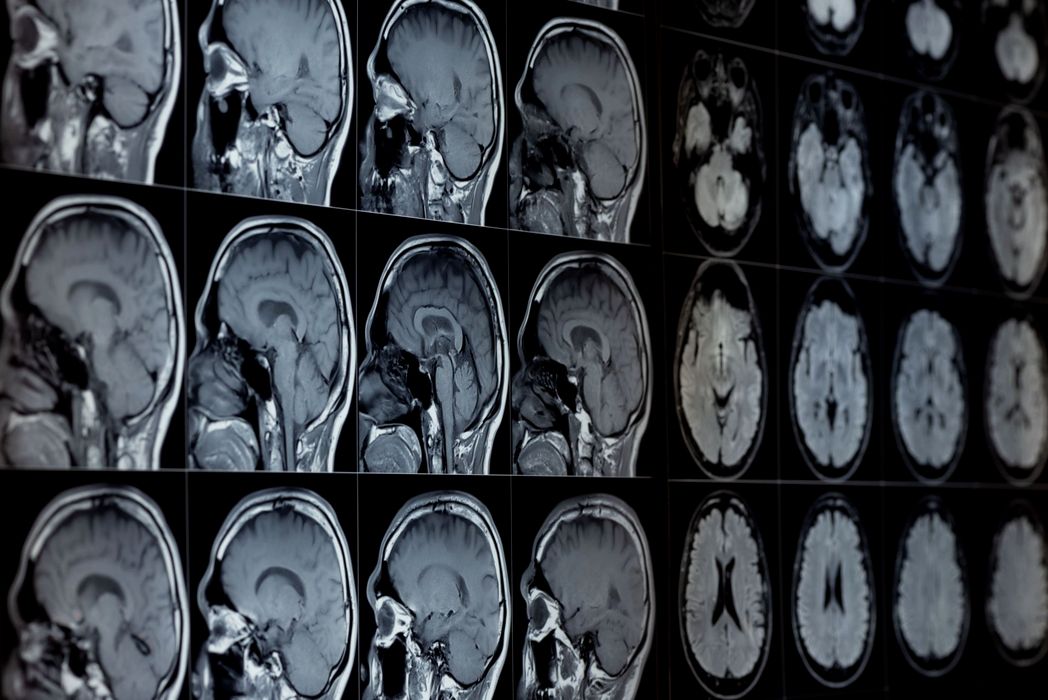

A fost găsit mecanismul prin care creierul evaluează experiențele sociale

A fost găsit mecanismul prin care creierul evaluează experiențele sociale. Cercetătorii de la Mount Sinai (SUA) au identificat pentru prima dată mecanismele neuronale din creier care reglează atât impresiile pozitive, cât și pe cele negative […]